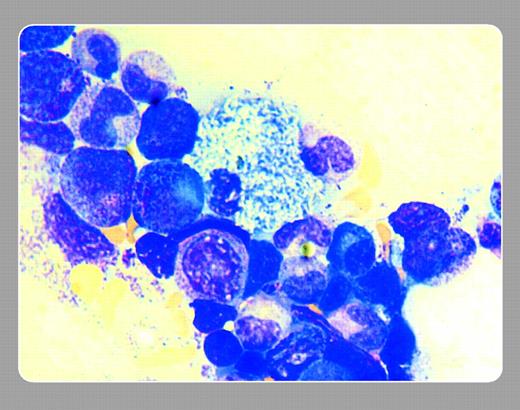

An African-American middle-aged HIV-positive woman with pancytopenia and clinical septicemia had a bone marrow examination. The marrow contained numerous macrophages resembling Gaucher cells, one of which is shown. A marrow stain for AFB identified organisms (Mycobacteria avium-intracellulare) within these macrophages (pseudo-Gaucher cells). This cause of pseudo-Gaucher cells has been described by R. Garza Guajardo, O. Barboza Quintana, and P. Perez Padilla (Diagn Cytopathol. 1998;19:462-464). This smear was provided by Dr Neil Abramson (Baptist Cancer Institute, Jacksonville, FL).FIG1

Neil Abramson, Baptist Cancer Institute